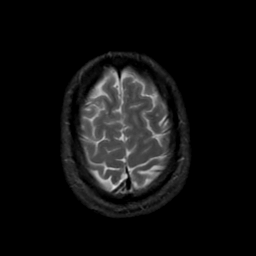

MR Study #20 October 6, 1991 -- Slice #43

[Home][Help][Clinical][Tour 1][Tour 2] Slice 43